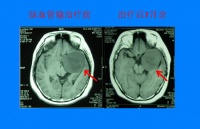

脑血管瘤治疗前后变化